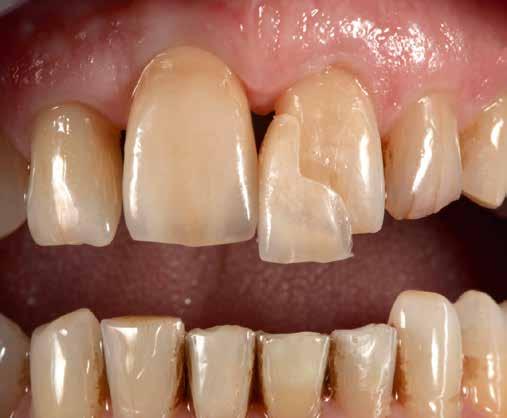

A CAD/CAM elterjedése ellenére az analóg eljárások nem szűntek meg funkcionálni. Esetbemutatásunk demonstrálja, hogyan rehabilitáltunk sikeresen az esztétikus zónában jól bevált munkamenettel, de új préskerámia recepttel. Az eredmény: természetes transzlucencia, opaleszcencia, fluoreszcencia – és egy boldog páciens.

A kiindulási helyzet recessziókkal és szabálytalan éli lefutással.

A pácienseset

Ötvenéves hölgy elégedetlen volt felső frontfogai esztétikai megjelenésével. Ezért elment a rendelőbe. Klinikailag vesztibulárisan két nagy kompozittömés volt megfigyelhető, széli elszíneződéssel. Az élek lefutása egyenetlen, aszimmetrikus volt. A frontfogakon recessziók és a nyakak szabaddá válása volt megfigyelhető. A hölgy a fogív gyors restauratív nivellálását kívánta. A nagymetszők közötti diasztémát csökkenteni kellett, de nem zárni, hogy megmaradhasson az optimális hossz-szélesség arány. A recessziók kötőszöveti fedését műtéttel kizárta. Viaszmintázat és intraorális mock-up segítségével szimuláltuk a teljes kerámiahéjakat, illetve segítettük a minimálinvazív preparációt a zománc területén. A páciens világos színű restaurációt akart. Vázanyagként a felső frontok területén a VITA AMBRIA anyagot terveztük használni, hogy a héjak életteli, színhelyes alapot kapjanak, egyidejűleg elérve az igen magas, 500 MPa-os szilárdságot. Az egyéniesítés megvalósítását VITA LUMEX AC leucit-erősítésű üvegkerámiával terveztük, hogy kevés, szín- és formastabil égetéssel reprodukálhassuk a fogakat. A 23-as szemfogat – palatinálisan megfigyelhető defektusa miatt – egyedüliként teljes koronával terveztük rehabilitálni, ugyanezzel az anyagkombinációval. A bukkális folyosó feltöltése érdekében a premolárisokra is héjak kerültek. Ezek természetes fluoreszcenciájának, transzlucenciájának és opaleszcenciájának eléréséhez monolit VITA AMBRIA munkákat készítettünk, felszíni festéssel.

Hajszálvékony viaszmintázat

Helyi érzéstelenítést követően preparálták a fogakat, enyhe kerekített vállal és ferdített éli kifutással a mock-up alapján. A preparálás konzekvensen kiterjedt a recessziós területekre is, ezek restauratív lefedése érdekében. Az 11, 21 és 22 fogakon gömb-gyémánttal vertikális behelyezőhornyot alakítottak ki. A lenyomatok alapján készült mester- és antagonista mintát beartikuláltuk a regisztrátum segítségével, és elkezdtük a laborban a tíz munkadarab megmintázását. Már a viaszmintázatok cervikális részén is nagyon gracilisan dolgoztunk, hogy morfológiailag is megfelelhessünk a minimálinvazív beavatkozás kihívásainak. A hat front- és négy monolitvázat hagyományos eljárással csapoztuk és beágyaztuk. A beágyazó megkeményedését követően előmelegítettük a beágyazást, majd VITA VACUMAT 6000MP kályhában A1 színű VITA AMBRIA HT anyagból préseltük le a munkát.

Behelyezés és összefoglalás

A klinikai próba során a hölgy mégis a központi diasztéma teljes zárását kérte, amit korrektúrégetéssel valósítottunk meg. A folysavazást és szilanizálást követően a kilenc héj és a korona adhezív módon, kompozittal került rögzítésre. A régi, jól bevált analóg módszer az új VITA AMBRIA receptnek köszönhetően hatékonyan valósította meg préskerámiával az esztétikus zóna rehabilitációját. A préskerámia természetes transzlucenciája, opaleszcenciája és fluoreszcenciája élő bázist adott az egyéniesítéshez és karakterizáláshoz. A préselés utáni minimális reakciós réteg gyors kibontást és kidolgozást tett lehetővé. A préskerámia robusztussága biztonságot hozott. Az optikai összhatás és összjáték a VITA LUMEX AC leplezőkerámiával hatékonyan segítette a páciensre jellemző finomságok megjelenítését. A hölgy nagyon elégedett volt új mosolyával.

A megváltoztatott recepttel a préskerámia még jobb lett.